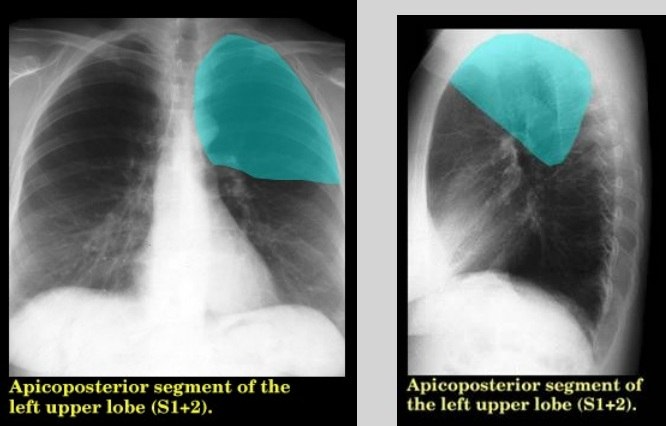

Анатомические изображения сегментов легких различных животных

Раздел: Другие животные